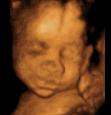

三维超声是在二维的基础上,增加表面成像功能,呈现的是立体图像。

四维彩超能看到宝宝在肚子里的动作和表情,想把彩超的图像作为宝宝人生的第一张照片来收藏,首选四维彩超~

在妈妈肚子里最舒服了,我睡的很香哦!